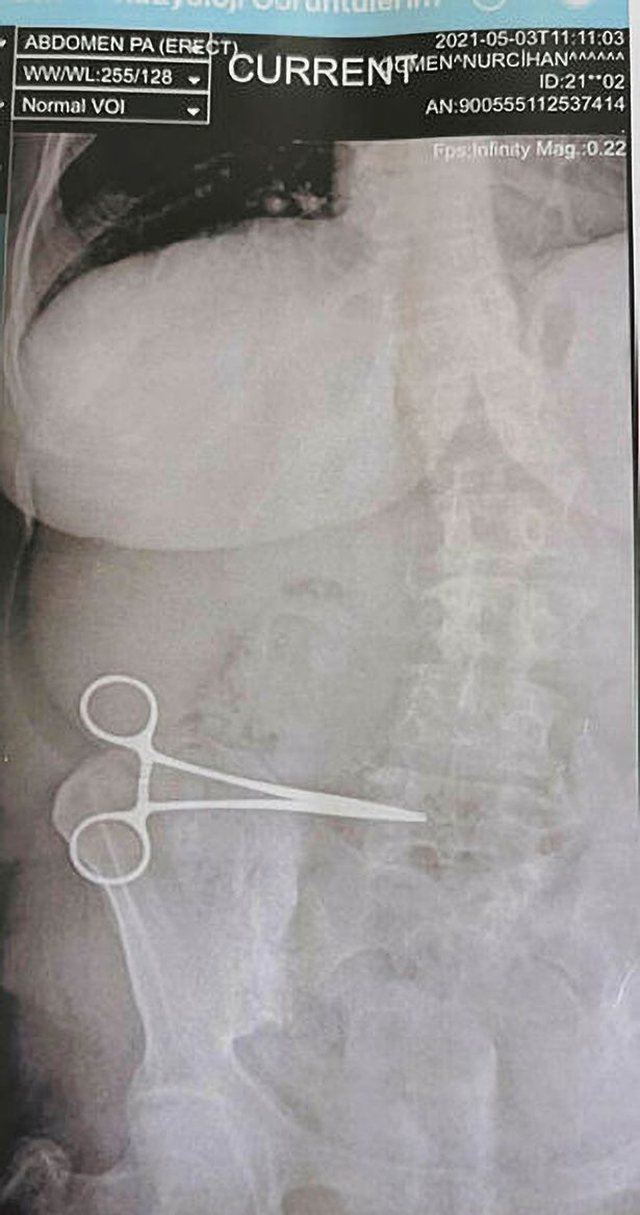

Më vonë ajo shkoi me burrin e saj Kubdettin Ogmen në Spitalin Shtetëror Soke pasi simptomat vazhduan për dy muaj. Një rreze X tregoi se Nurcihan kishte një gërshërë të lënë në bark.